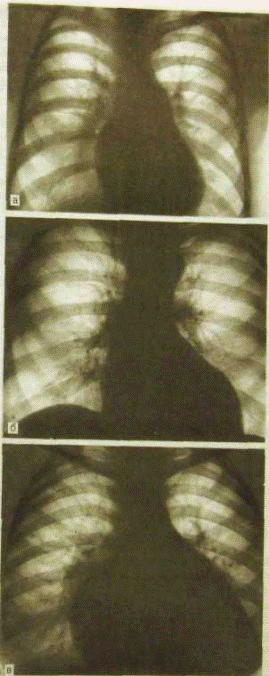

а — митральная; б — аортальная; в — трапециевидная (треугольная).